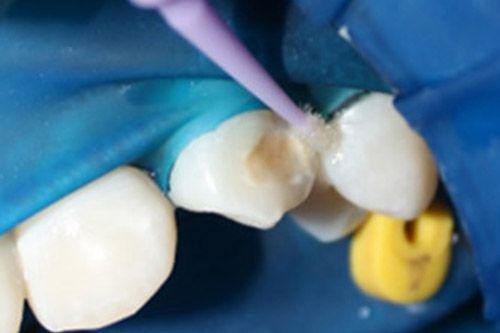

Se decidió utilizar un aeropulidor con bicarbonato Detarfar de Eufar por 1 minuto, con la finalidad de remover el tejido afectado.

Se observó que una cavidad se había formado, los bordes de esta se grabaron con Icon etch por 2 minutos.